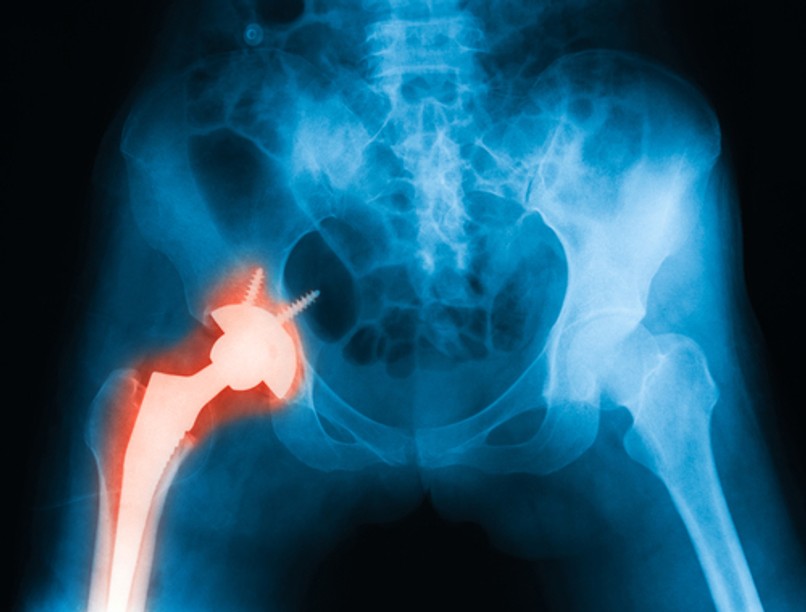

Titán csontpótlásokat fejlesztenek, amik teljesen összépülnek a csonttal - az ábrán a hagyományos, csavaros módszer látszik.

A professzor kiemelte: cél, hogy olyan implantátumokat tudjunk készíteni, amelyeket nem csavarok és egyéb műszaki megoldások tartanak, hanem összeépülnek a csonttal.